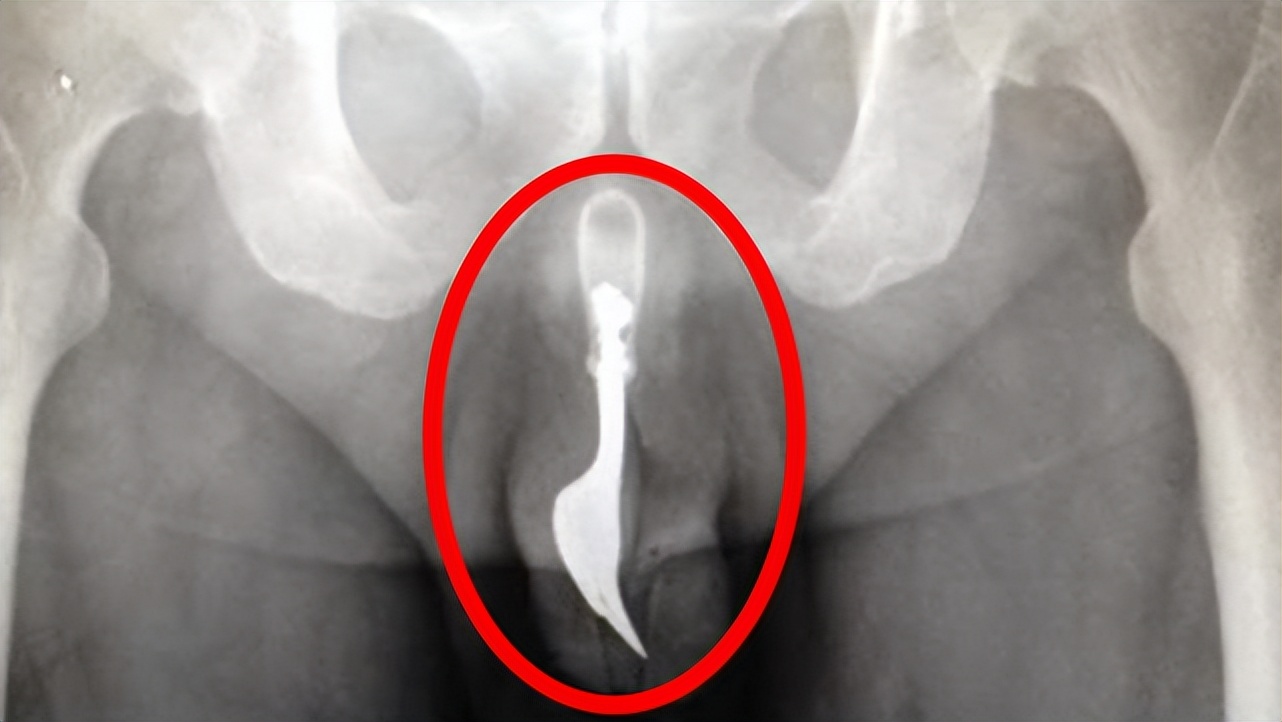

不仅如此,牙签鱼钻进人类体内以吸血为生。一旦扎根之后,它们将伸出一根小刺,并靠吸取受害人的血液和身体组织为食。并且,将在受害人体内一直存活下去并不断繁殖,直到将受害人的血吸干为止,而只有外科手术才能将它们清除。

牙签鱼成体小于10厘米,在面对食物链顶端的人类一样毫不畏惧,并且能够钻进男性的尿道和女性的阴部,一旦进入将会人的体内,牙签鱼将会扎根于此,开始吸血繁殖,直到吸食干才愿意离开。

因此,需要借助外科手术将其从身体内清除,才能保护寄主的生命安全。如果不能及时进行外科手术,只能等待牙签鱼蚕食身体,致人死亡,人类在它们面前不过是一口急需畅饮的琼浆。